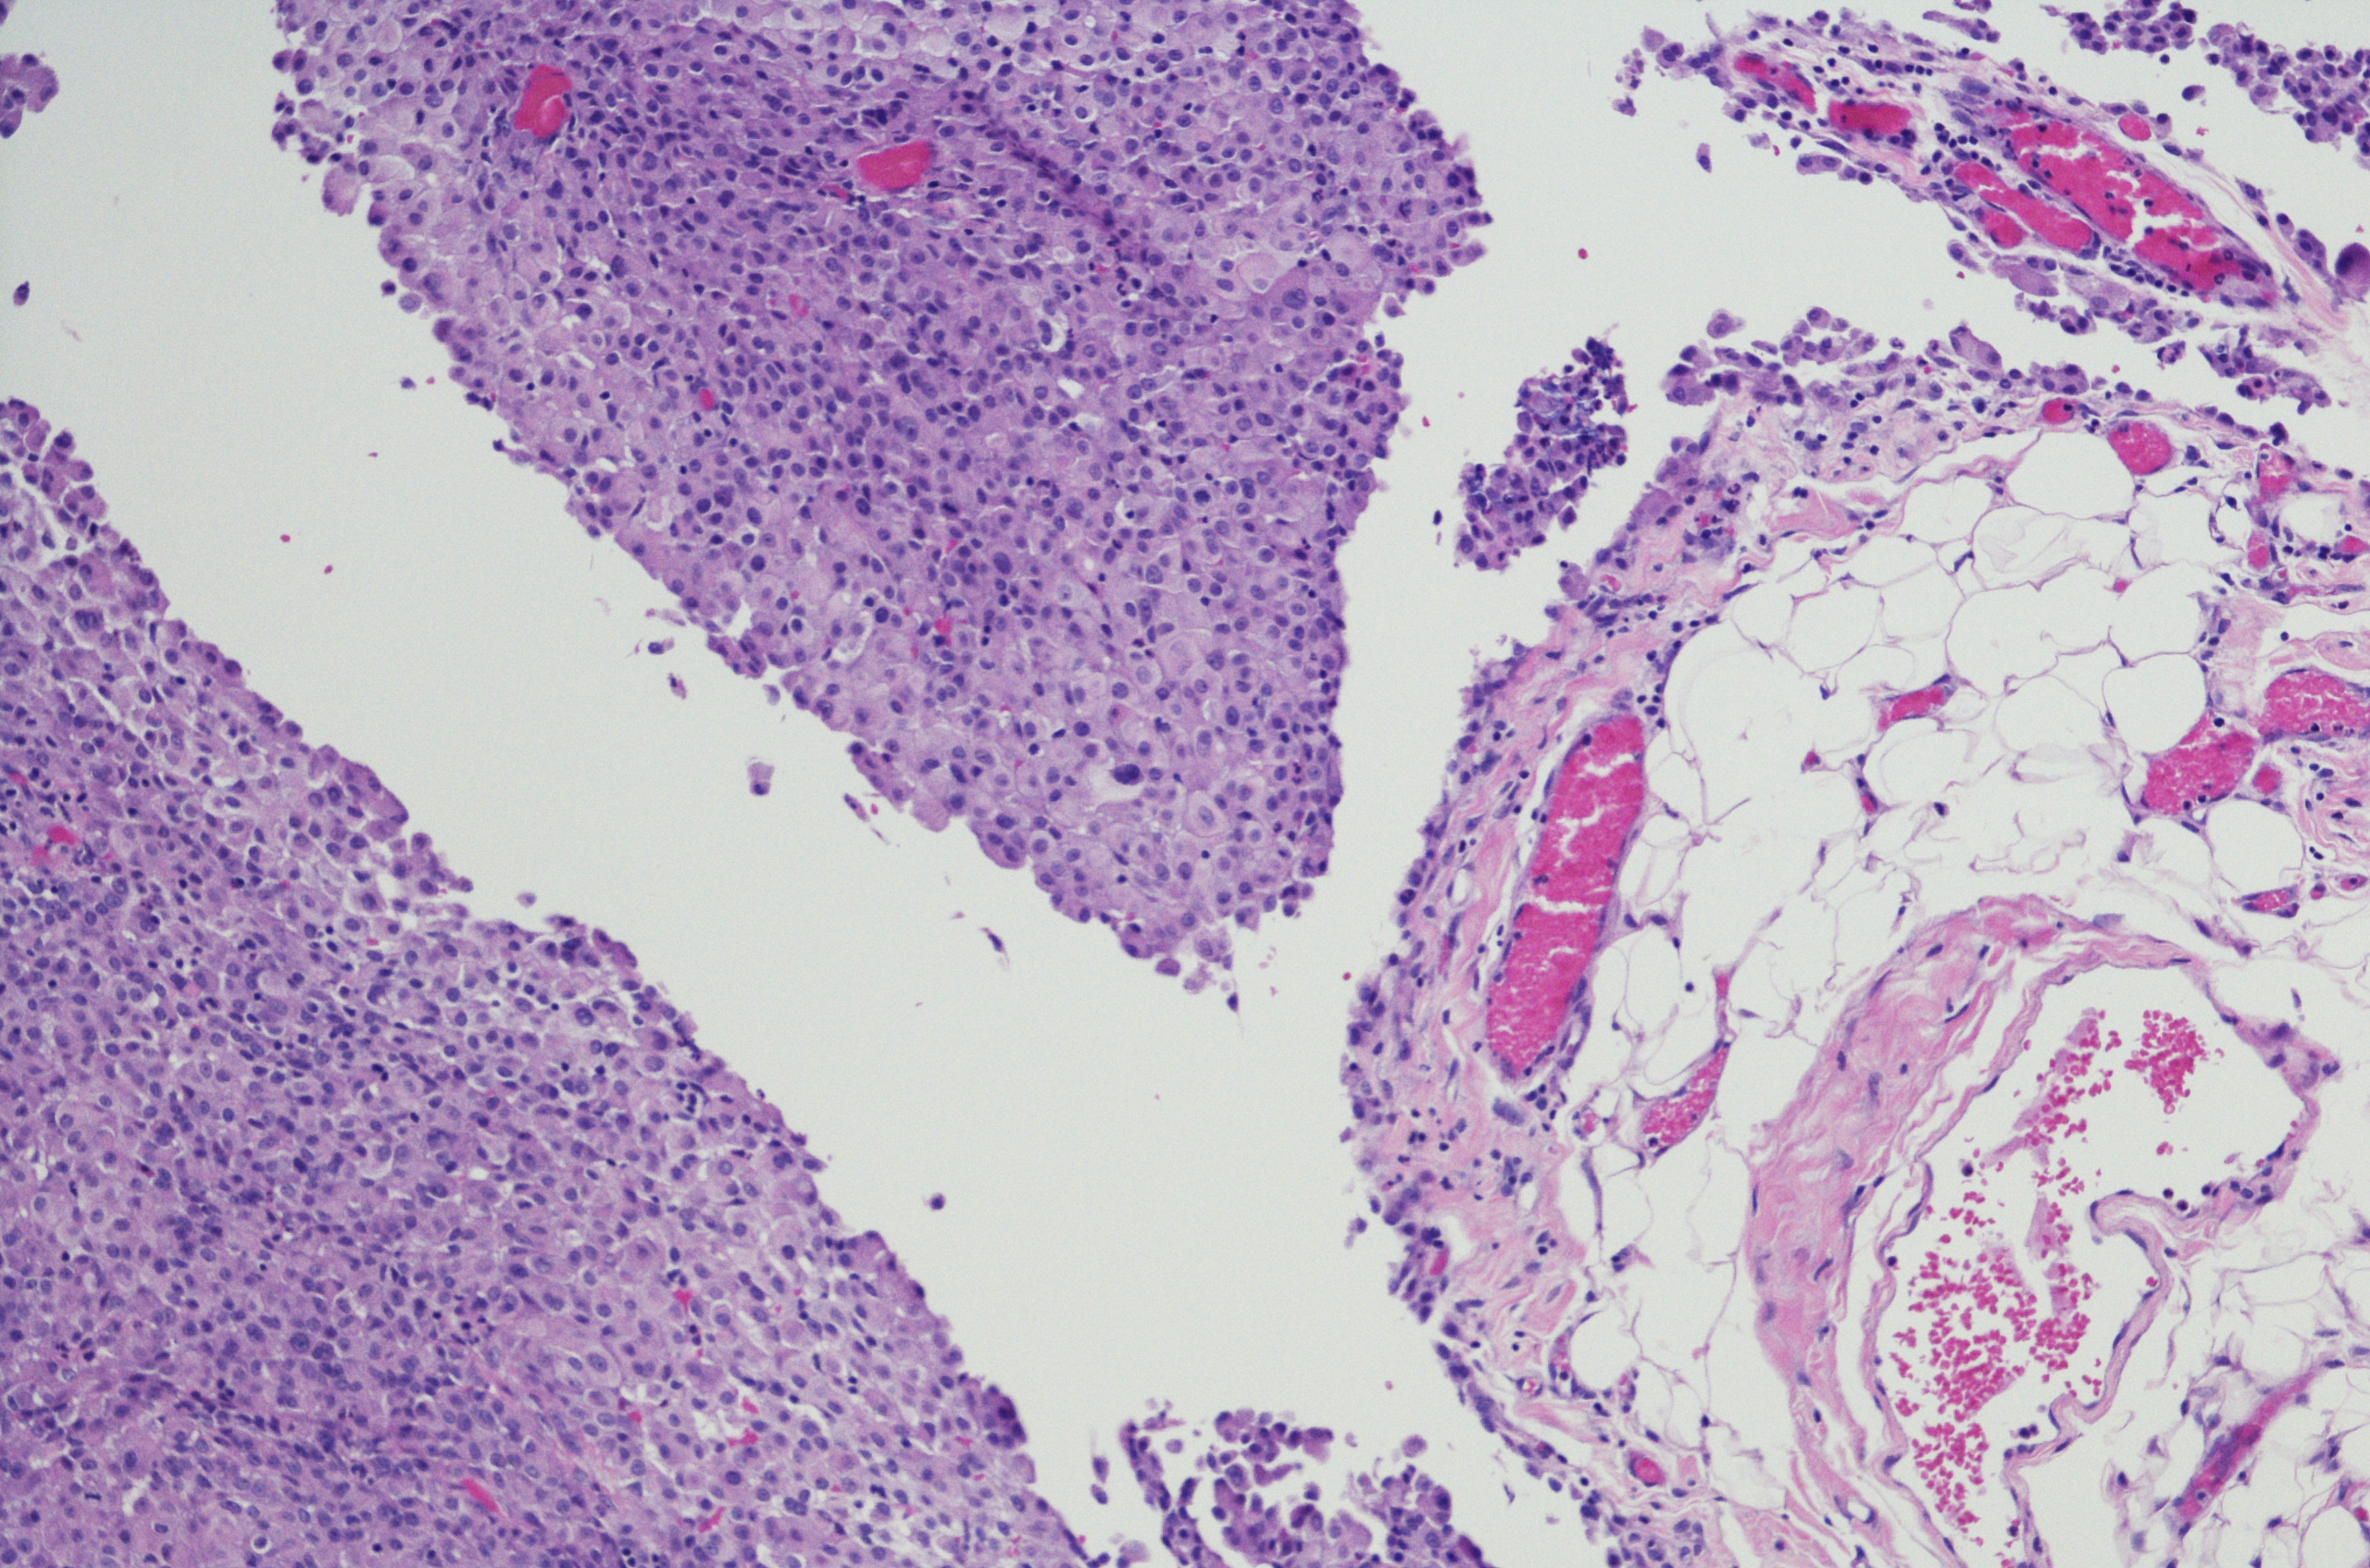

Diagnosis of Peritoneal Cancer is done via a specialist, using tests including a biopsy.